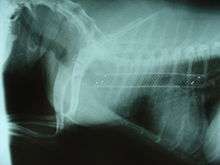

Symptoms include a cough (often called a "goose honk cough" due to its sound), especially when the dog is excited. This cough is usually paroxysmal in nature. Other symptoms include exercise intolerance, respiratory distress, and gagging while eating or drinking. Tracheal collapse is easily seen on a radiograph as a narrowing of the tracheal lumen. Treatment for mild to moderate cases include corticosteroids, bronchodilators, and antitussives. Medical treatment is successful in about 70 percent of tracheal collapse cases.[4] Severe cases can be treated with surgical implantation of a tracheal stent (inside or outside of the trachea) or prosthetic rings. Extraluminal (outside the trachea) stenting is generally only used for tracheal collapse in the neck region. Intraluminal stenting has shown more promise for success with intrathoracic cases, especially using nitinol, a type of shape memory alloy composed of nickel and titanium. Potential problems include stent migration and fracture.[5]